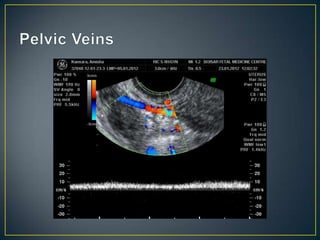

• Pelvic Congestion Syndrome postulated as cause of

chronic pelvic pain

• Venography is the gold standard

• However, ultrasound can still be used for diagnosis

• Dilated ovarian vein > 5 mm

• Tortuous veins around ovary and uterus (> 5mm)

• Venous plexus crossing from one side to another

• Change of flow direction with Valsalva maneuver

• Increase in size of veins with Valsalva maneuver

• Pelvic CongestionSyndrome postulated as cause of chronic pelvic pain • Venography is the gold standard • However, ultrasound can still be used for diagnosis

• 67.

• Dilated ovarianvein > 5 mm • Tortuous veins around ovary and uterus (> 5mm) • Venous plexus crossing from one side to another • Change of flow direction with Valsalva maneuver • Increase in size of veins with Valsalva maneuver